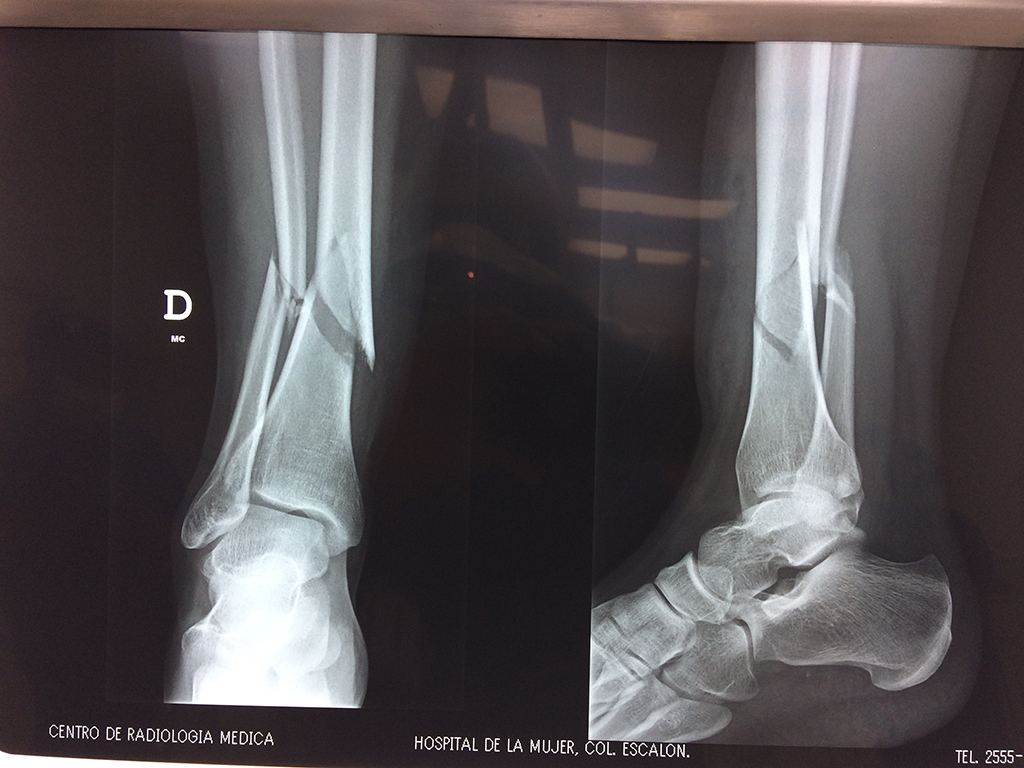

Cirugías de Hombros - Perone y Tibia

Aunque cada uno de estos huesos puede fracturarse por separado, normalmente la rotura es una lesión que se produce de forma conjunta

La mayor parte de las roturas implican a la parte proximal del hueso (parte del hueso próximo a la rodilla) o a la parte distal (parte del hueso cerca del tobillo).

Debido a la fina cobertura de piel que recubre la tibia y el peroné, las fracturas generalmente son abiertas, es decir, el hueso roto rasga la piel, atravesándola. Las fracturas de tibia y peroné generalmente se producen por un fuerte impacto o torsión.